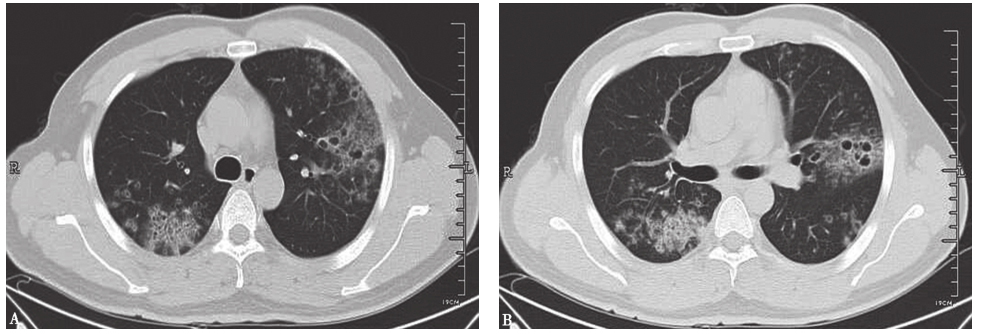

图2侵袭性肺曲霉菌病胸部CT表现

男性患者,53岁,发热、咯血1周,伴呼吸困难,诊断为侵袭性肺曲霉菌病。胸部CT初期表现为沿支气管分布的粟粒样结节(A);1周后表现为多发沿支气管分布的空洞,有中心性支气管扩张(B)

图3血源性金黄色葡萄球菌肺炎胸部CT表现

胸部CT可见双肺多发结节空洞性改变,部分空洞伴液平,病灶周围可见渗出表现